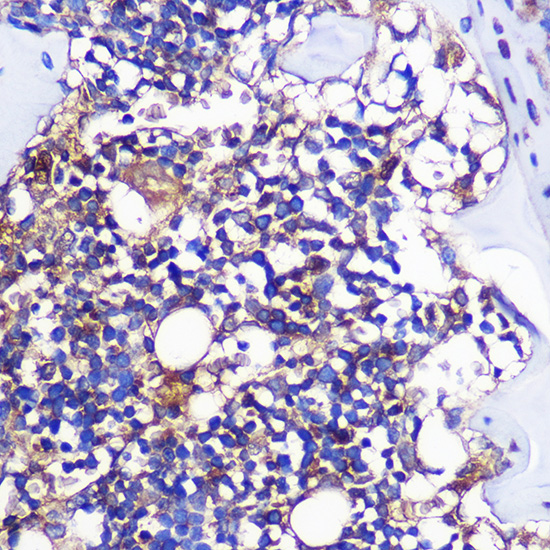

![CCR1 antibody [HL2840] detects CCR1 protein at cell membrane and cytoplasm by immunohistochemical analysis. Sample: Paraffin-embedded human breast carcinoma. CCR1 stained by CCR1 antibody [HL2840] (GTX640111) diluted at 1:100. Antigen Retrieval: Citrate buffer, pH 6.0, 15 min](https://www.genetex.com/upload/website/prouct_img/normal/GTX640111/GTX640111_T-45355_20240412_IHC-P_24043002_864.webp)